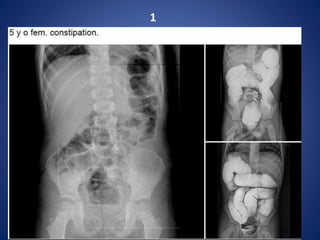

1

Total Colonic Aganglionosis—Long Segment

Hirschsprung Disease

Hirschsprung disease ---

It can be anatomically divided into 4 types according to the length

of the aganglionic segment:

• short segment disease : ~ 75% *

rectal and distal sigmoid colonic involvement only

• long segment : ~ 15%

typically extends to splenic flexure / transverse colon

• total colonic aganglionosis : 2 - 13%

also known as Zuezler-Wilson syndrome

occasional extension of aganglionosis into small bowel

• ultrashort segment disease

3 - 4 cm of internal anal sphincter only